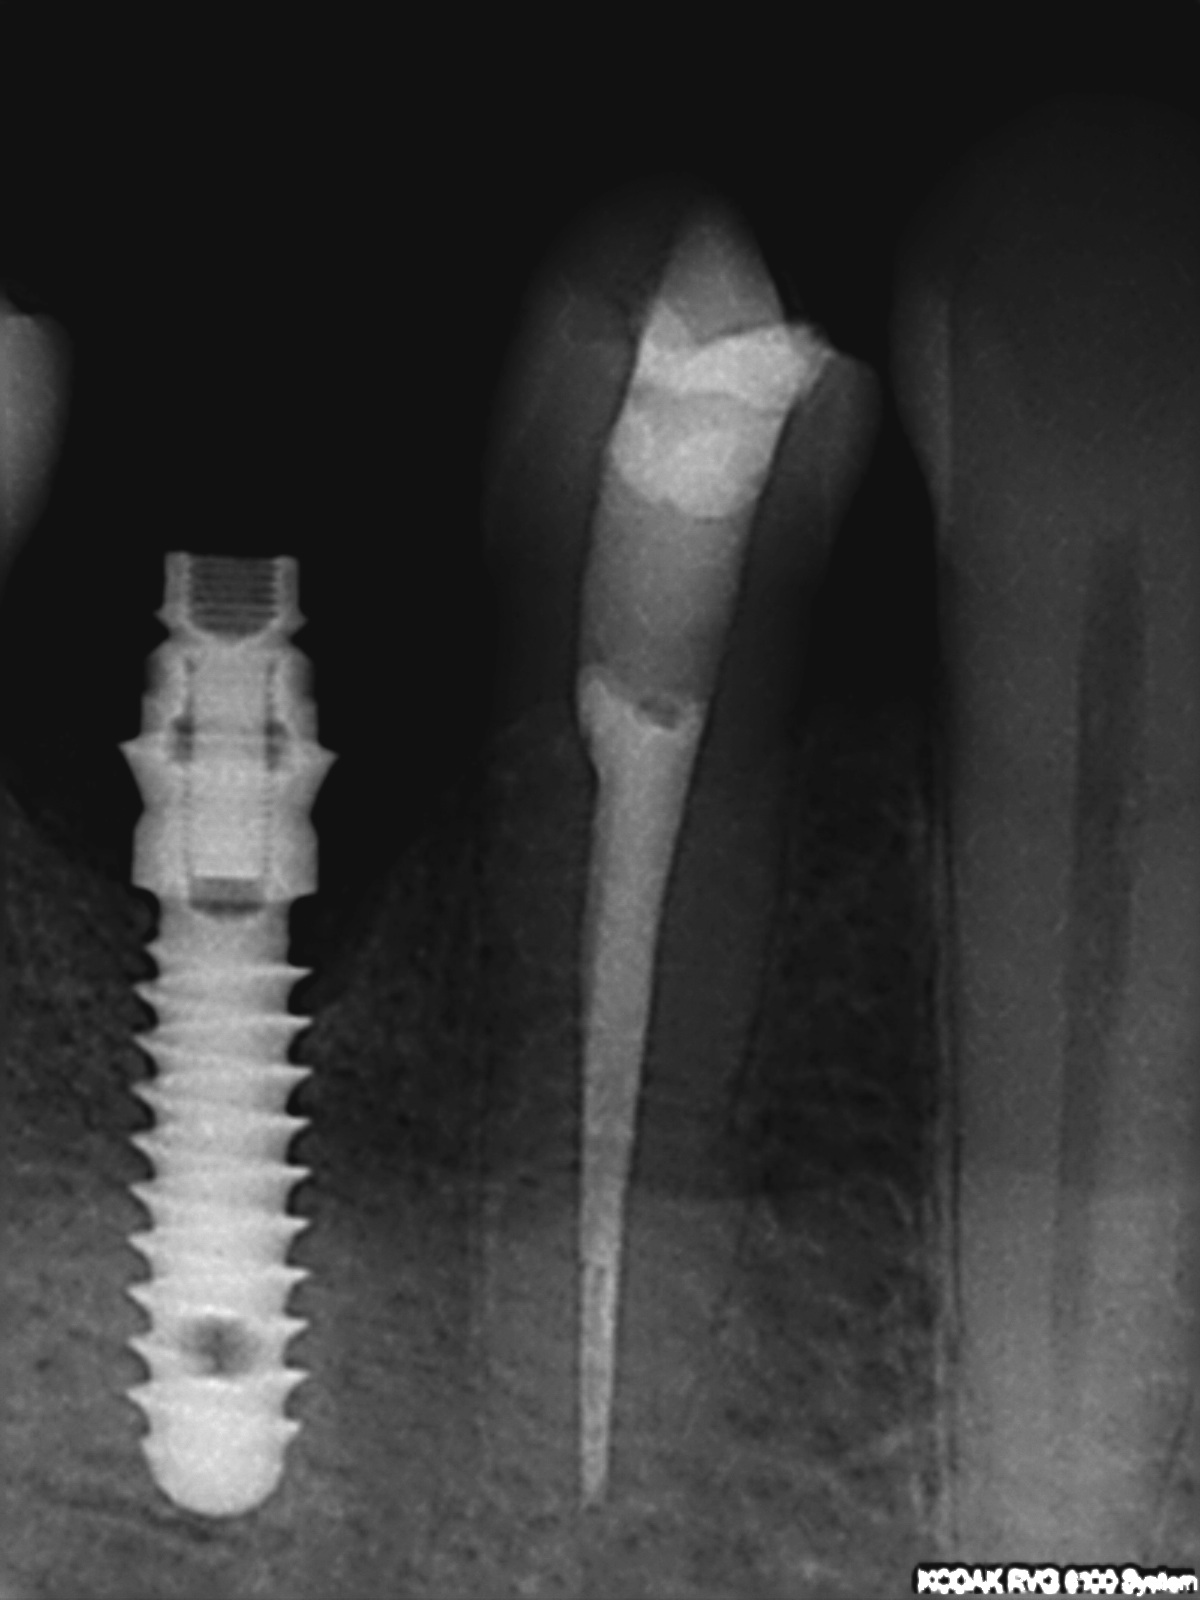

R4

1200 × 1600

Endorevision

Abschlusskontrolle